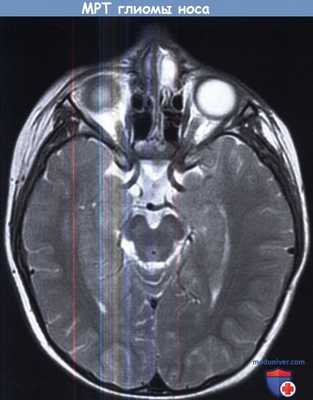

а) Диагностика глиомы носа. При внутриносовом расположении требуется использование лучевых методов. Наиболее чувствительным и информативным исследованием является МРТ, с помощью которой можно определить интракраниальное распространение глиомы и дифференцировать с энцефалоцеле. Они характеризуются гиперинтенсивным сигналом в режиме Т2, интенсивность в режиме Т1 вариабельна.

В дополнение к МРТ возможно использование КТ, на которой глиомы изоденсивны. КТ позволяет оценить отношение глиомы к внутриносовым структурам и помогает в планировании хирургического лечения.

3. МРТ при глиоме носа:

• Т1ВИ:

о Объемное образование преимущественно смешанной или низкой сигнальной интенсивности

о Редко визуализируются извилины коры (серое вещество)

• Т2ВИ:

о Гиперинтенсивный сигнал, обусловленный глиозом

о Ликвор вокруг образования, сообщающийся с субарахноидальном пространством, отсутствует

• Т1ВИ С+:

о Диспластическая ткань обычно не накапливает контраст:

- Периферическое контрастирование интраназального образования может быть обусловлено слизистой оболочкой носа

4. Рекомендации по визуализации:

• Лучший метод визуализации:

о Мультипланарная МРТ:

- Может обнаруживаться ножка из фиброзной ткани (не паренхима мозга) между ИНГ и полостью черепа

- МРТ лучше, чем КТ, для дифференциальной диагностики ГН и цефалоцеле или дермоида

- Позволяет избежать облучения радиочувствительного хрусталика у молодых пациентов

• Выбор протокола:

о Тонкосрезовая сагиттальная МРТ (Т1 и Т2)

о Перед операцией: тонкосрезовая аксиальная КТ в костном окне с корональными реформациями для планирования операции:

- Только кости не накапливают контраст